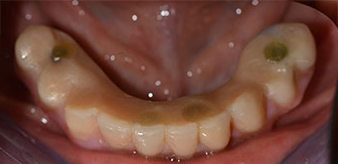

Die 64-jährige Patientin wurde mit einer Unterkiefer-Restbezahnung 38, 33 und 43 und einer klammerbefestigten Interimsprothese im Unterkiefer vorstellig (Abb. 1 und 2).

Unterkiefer-Restbezahnung

Abb. 1

Abb. 2